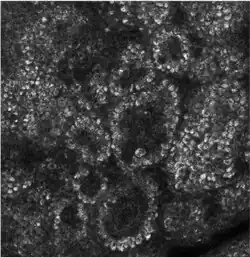

Confocal image of the stratum basale already showing some papillae

Composed mainly of proliferating and non-proliferating keratinocytes, attached to the basement membrane by hemidesmosomes, focal adhesion. Melanocytes are present, connected to numerous keratinocytes in this and other strata through dendrites. Merkel cells are also found in the stratum basale with large numbers in touch-sensitive sites such as the fingertips and lips. They are closely associated with cutaneous nerves and seem to be involved in light touch sensation.[11]